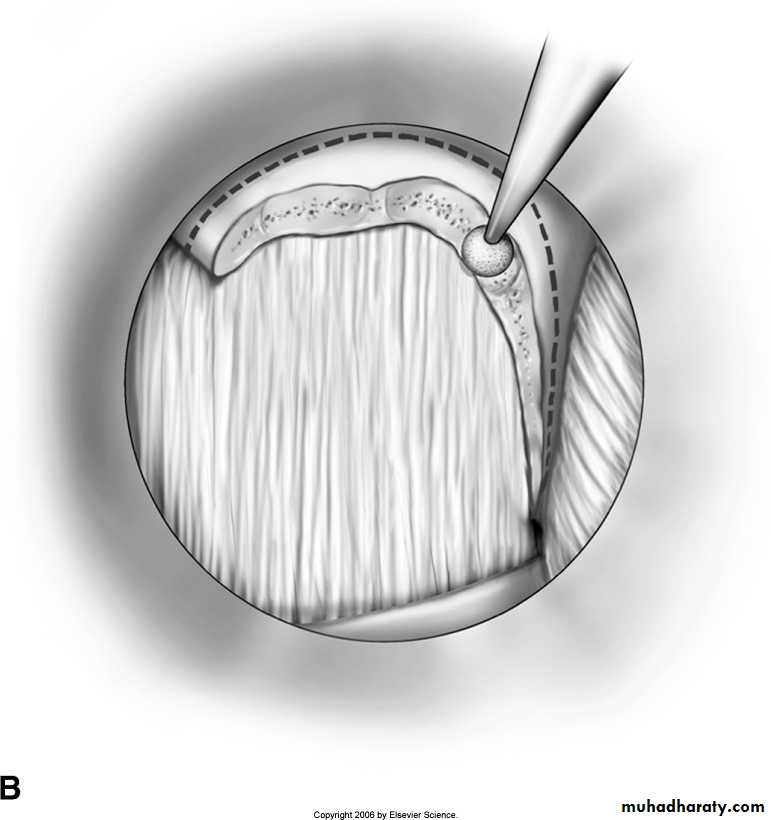

- open laminectomy with discectomy

- micro discectomy

Surgery